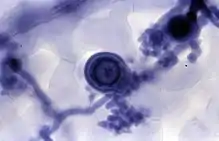

Observation with an optical microscope of Hyaloperonospora parasitica within a leaf of Arabidopsis thaliana by using the trypan blue staining.

Trypan blue is commonly used in microscopy (for cell counting) and in laboratory mice for assessment of tissue viability.[5] The method cannot distinguish between necrotic and apoptotic cells.

It may be used to observe fungal hyphae[6] and stramenopiles.